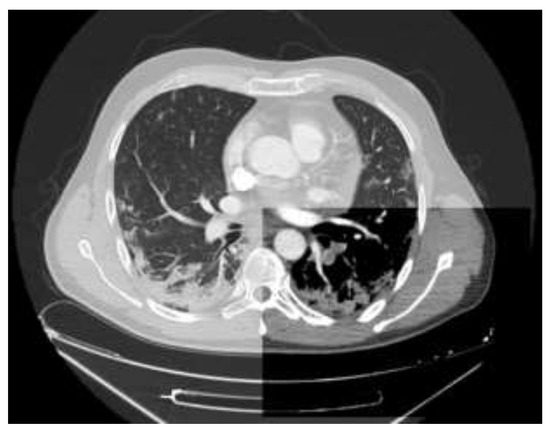

Pulmonary CT Angiography